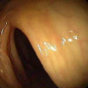

More than 15 million colonoscopies are performed in the US every year [1, 2]. During these procedures, 22-28% of polyps and 20-24% adenomas are missed [3]. There are no commercial or automated tools available to assist endoscopists in gauging the amount of colon surface missed during optical colonoscopy (OC) procedures. The main culprit in substandard coverage during colonoscopy are the sharp bends and haustral folds, as depicted in Figure 1a. Even though the endoscope tip can be flexed to look behind folds and sharp bends, beginner or tired endoscopists might not use this option wisely and may have a high miss rate. This high miss rate can be reduced if endoscopists have a visualization tool to identify and investigate areas occluded by haustral folds.

| (a) | (b) | (c) | (d) |

In this paper, we present a deep learning model for realtime visualization of missed colon surfaces directly on the colonoscopy video frames without doing any prior offline 3D reconstruction using contiguous sets of frames. Specifically, we make use of prior 3D reconstructed virtual colonoscopy (VC) [7, 8] data, created from a computed tomography (CT) scan, to produce training data for missing surface visualization (Figure 1b–d). This is used in conjunction with OC data for the same patient to drive an unpaired image-to-image translation with a modified lossy CycleGAN [4] and a new enforced shared OC and VC latent space representation. The lossy CycleGAN [4] by itself overfits due to the sparse training data for the missing surface task (most OC frames have no or few missing surface green pixels as opposed to the dense depth maps for which the lossy CycleGAN was originally proposed) and can easily hallucinate structures which do not exist, as shown in Figure 1. Adding a shared latent space forces the network to preserve structures (and avoid hallucination) when translating between domains. With added Gaussian noise, we also show that the same framework with shared latent space representations can be used to generate realistic one-to-many mappings from VC to OC and OC to OC for augmenting OC datasets in computer-aided detection and classification pipelines.

In order to create training data for per-frame missing surface visualization, the opacity of the 3D colon mesh is lowered such that the more opaque regions indicate the missed surfaces, which are colored green in Figure 1c. The per-frame missing surface data is generated through Blender and example videos are provided111Supplementary Video: https://youtu.be/x1-wwCiYeC0. Figure 1 shows a typical colon anatomy along with the haustral folds and the pictorial representation of a missed surface for a certain endoscope camera position. To aid the model with the image-to-image domain translation task, we added the missing surface information in green channel on top of the VC rendering of the colon (Figure 1d).